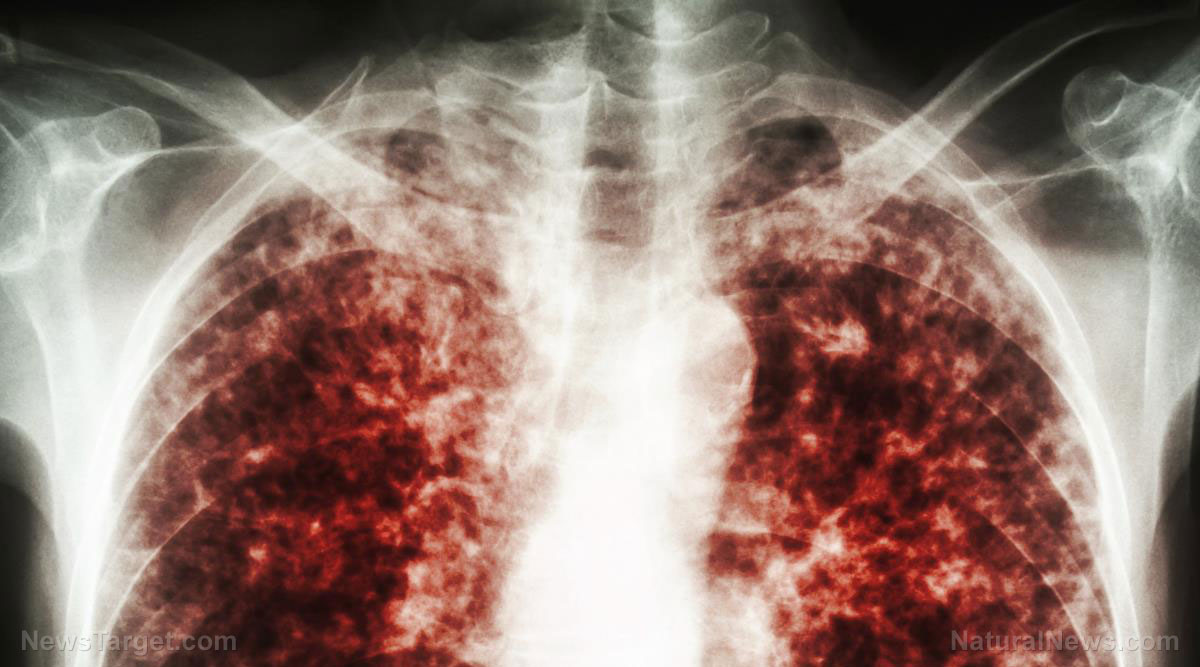

NYC sees a surge in TUBERCULOSIS cases amid influx of migrants

A significant increase in tuberculosis (TB) cases in New York City (NYC) raises concerns about the potential resurgence of this highly contagious airborne disease in the United States. So far this year, initial data shows there have been approximately 500 new TB cases officially diagnosed in the city alone – the highest number of cases […]

JUVENILE BIOWEAPONS: Federal gov’t released nearly 2,500 illegal immigrant kids with latent TB into the US

The U.S. government has reportedly released nearly 2,500 illegal immigrant children with latent tuberculosis (TB) infections into 44 states over the past year without providing assurances of treatment. According to a court-ordered report on the treatment of these children, approximately 126,000 children were released and an alarming infection rate of one in 50 migrant children […]